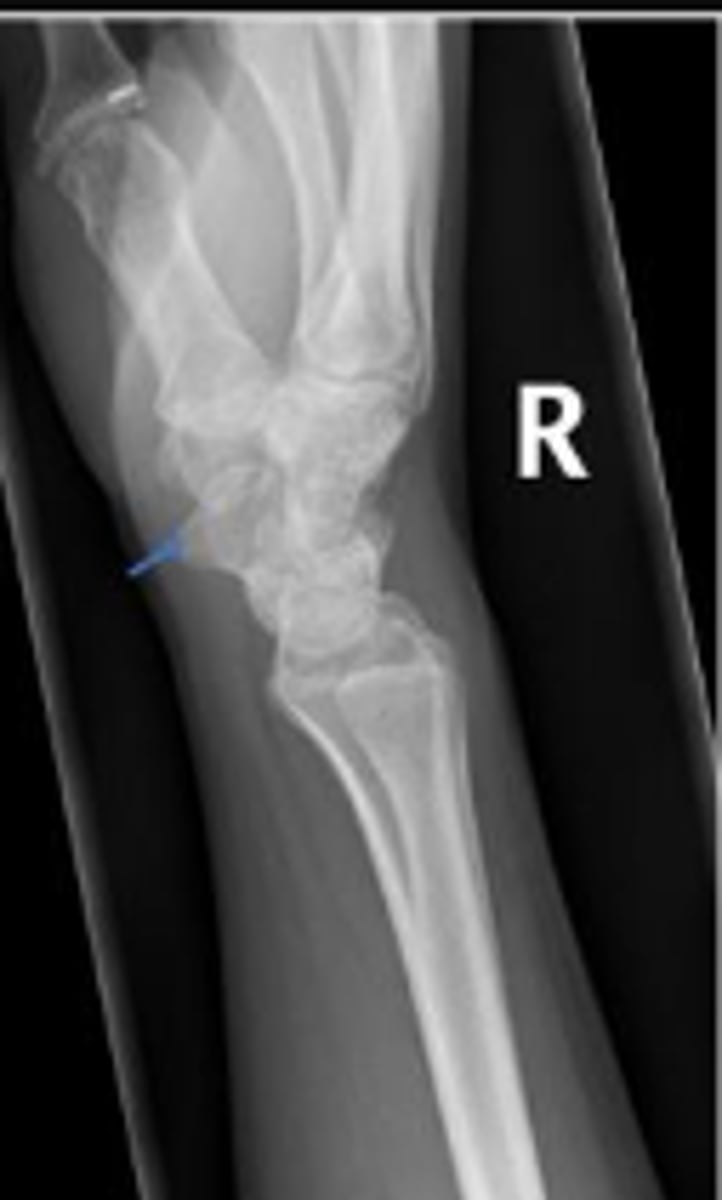

Medial oblique of the right wrist

What is the name of the radiographic view?

Right scaphoid

What is outlined?

What is the arrow pointing to?

What is the arow pointing to?

DRUJ